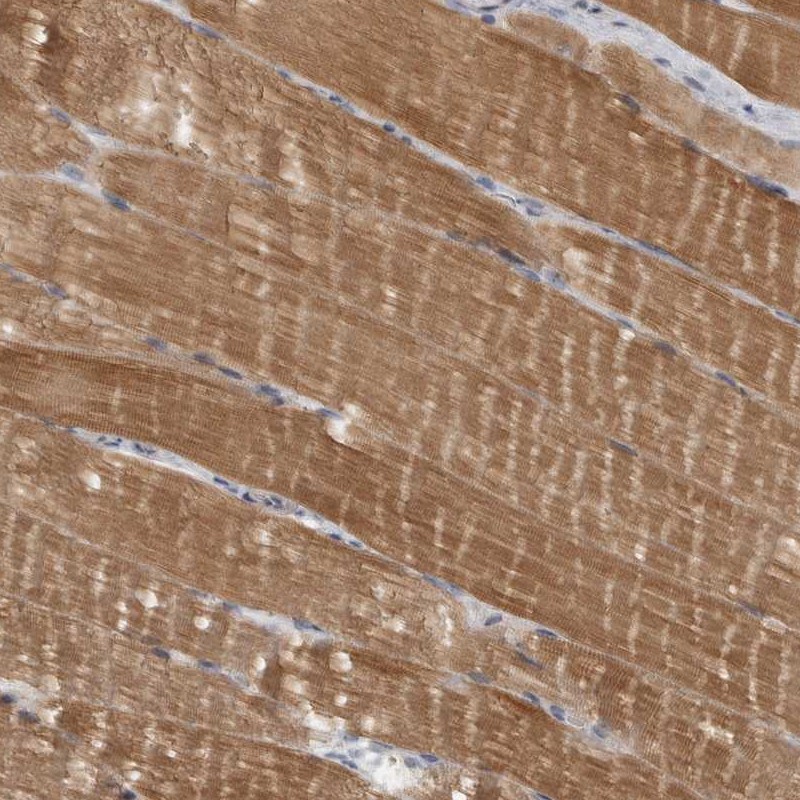

Immunohistochemical staining of human skeletal muscle shows moderate cytoplasmic positivity.